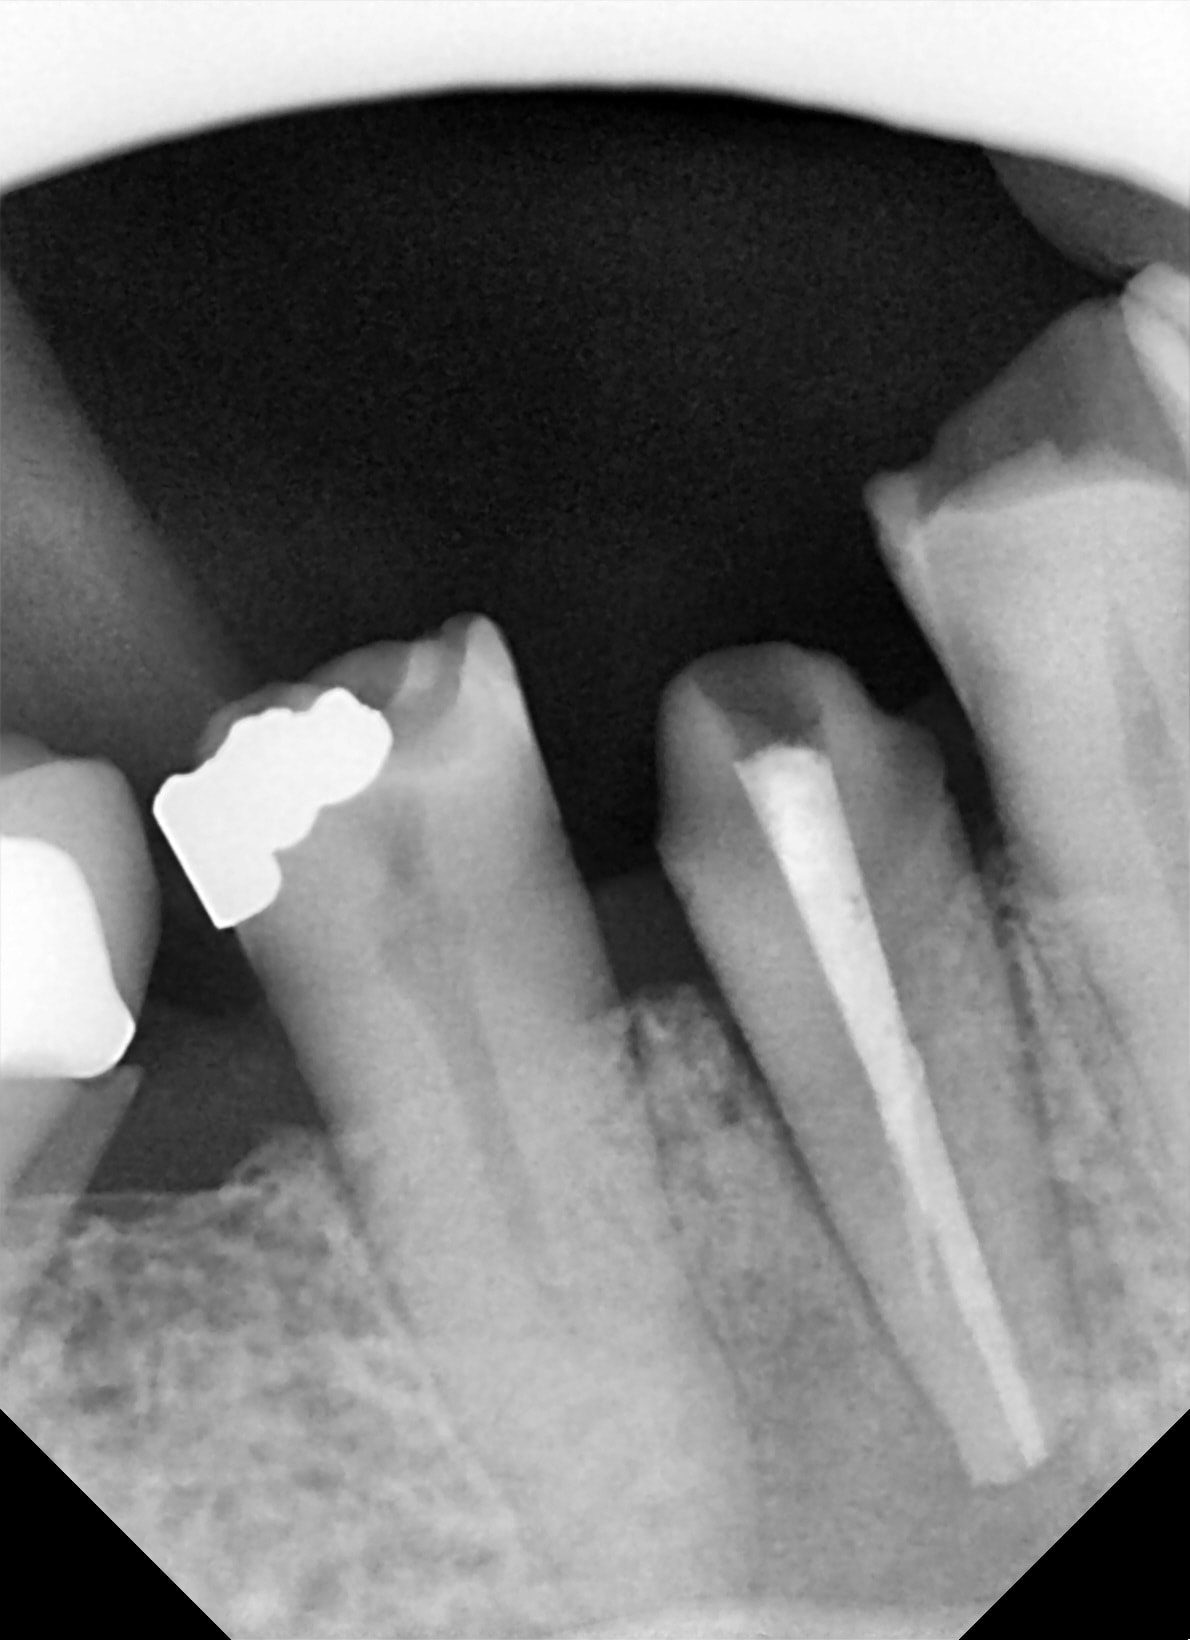

Tu vois la ligne d escalier horizontale sur tout le cliche. Mais rien n est impossible...

C’est un artefact qui se voit au niveau de la molaire aussi et surtout sur l’autre PM!

Sinon j’aurais posé un implant directement sans passer par la case départ Daryl , tu penses bien :)